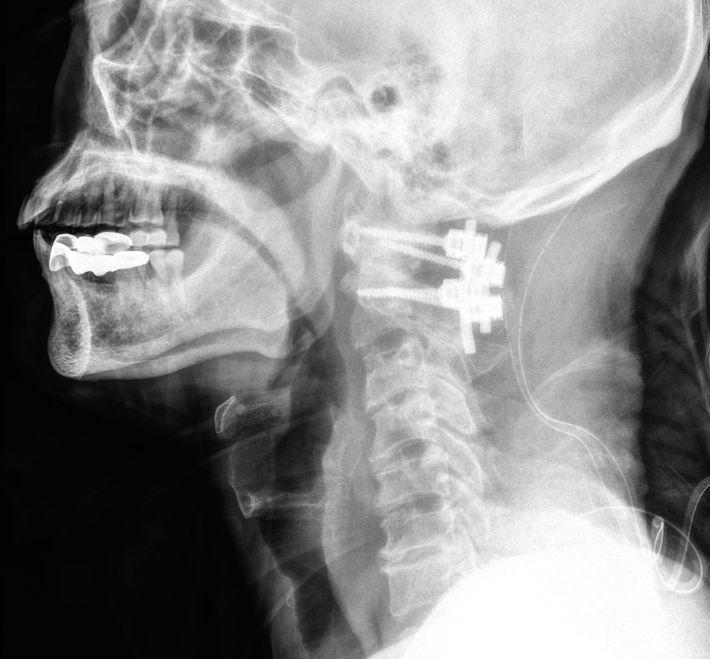

頸椎微創手術完整指南:解析「導航微創」如何精準解除神經壓迫、加速復原

手麻、走路不穩、神經壓迫怎麼辦?頸椎微創手術結合3D電腦導航與高解析內視鏡,打造安全、低風險、快速復原的頸椎治療方案。了解張建鈞醫師團隊如何為您量身打造個人化手術計畫!